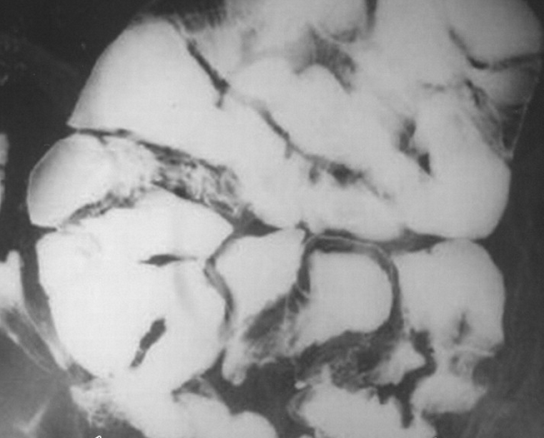

Figure 2 . Abdominal CT scan shows markedly dilated stomach with mass-like, thick-walled bowel loops (red arrow). ( Courtesy Dr . V . Penopoulos ) .